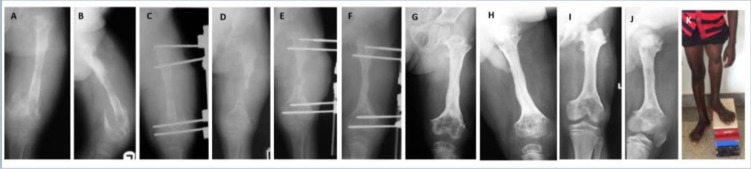

Abstract Image

Background. Post-osteomyelitis bone defects represent a challenging clinical situation. This retrospective cohort study was designed to evaluate the long-term outcome of the use of non-vascularized bone grafts in the management of such defects in children. Methods. Twenty-three children (mean age 7 years, range 2-13 years) were studied. All of the defects were segmental (mean defect length 6 cm, range 3-12 cm), involving the tibia, femur, humerus and radius. Fifteen children presented with an active infection and were managed with a staged protocol. The first stage included sequestrectomy or debridement of the site. The second stage, i.e. the graft procedure, was performed after 12 weeks on average. The mean follow-up was 9.2 years (range 7-15 years). Results. Bone union was primarily achieved in 14 children (61 %). Complications were experienced in the remaining nine children. Conservative and surgical treatment led to bone union in all patients within 5 years of the index procedure. Recurrence of infection was observed in two patients (8.7 %). All of the children were able to use the limb at the final follow-up; only three required the use of a brace. Conclusions. Autogenous non-vascularized bone graft may be considered a valid option in the treatment of bone defects secondary to osteomyelitis in children.